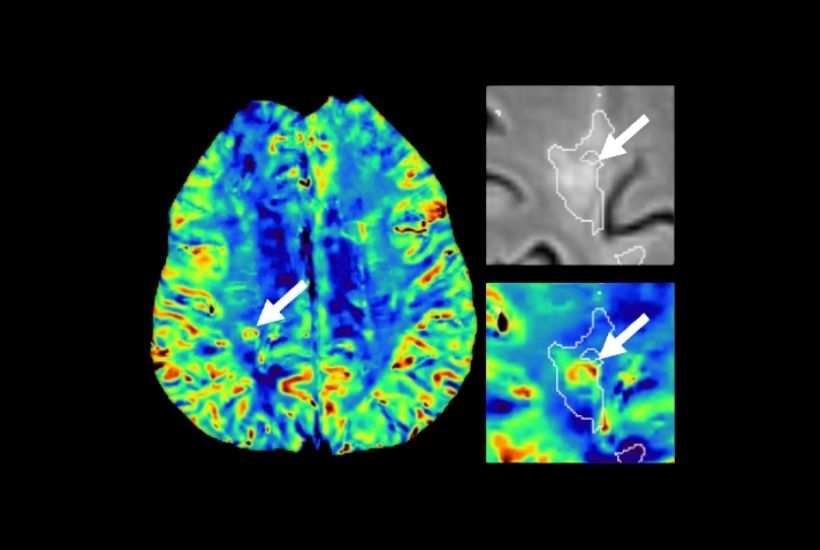

INRIA x CHU RENNES

SCLÉROSE EN PLAQUES

Objectifs et résultats

Une meilleure caractérisation des lésions cérébrales et médullaires :

- signes du halo paramagnétique et de la veine centrale : mécanismes inflammatoires

- magnétisme de la gaine de myéline